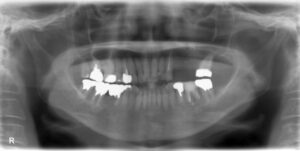

上顎小臼歯2本欠損症例

BEFORE AFTER 51歳男性/上2本欠損/インプラント埋込手術 【治療内容】 右上第一小臼歯、第二小臼歯を数年前…